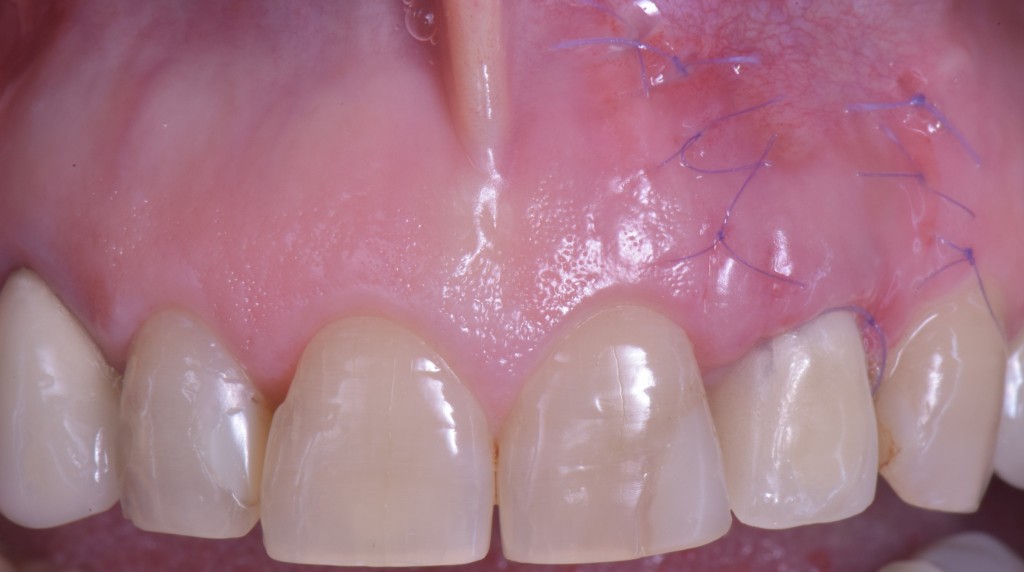

gestione dei tessuti molli - risoluzione della fistola

E quando il tessuto gengivale è di nuovo sano risolviamo il problema estetico. Con un intervento che mi ha richiesto un’oretta solo perché ho dovuto fare una ripresa sensazionale in 4K dove si vedono pure le cellule, ma se mi fossi accontentato di qualche foto ci avrei messo poco più di mezz’ora. Questo non perché io sono veloce ma perché è una chirurgia smart, una chirurgia poco invasiva.

corso gestione tessuti molli - guarigione 1

corso gestione dei tessuti molli - guarigione 2

Ti mostro la foto a sette giorni per due motivi.

• La bellezza di una chirurgia si valuta dalla guarigione a sette giorni. Se aspetti 2 anni, alla fine anche una chirurgia di merda guarisce.

• Ho operato la paziente 7 giorni fa e non ho foto più recenti ma penso che concorderai con me che dopo una guarigione così difficilmente avremo delle sorprese.

Come puoi vedere abbiamo risolto completamente il deficit dei tessuti molli che era stato lasciato dopo le precedenti terapie e…

… posto le basi per una nuova riabilitazione definitiva che si possa definire esteticamente degna dei tempi in cui abbiamo la fortuna di vivere.